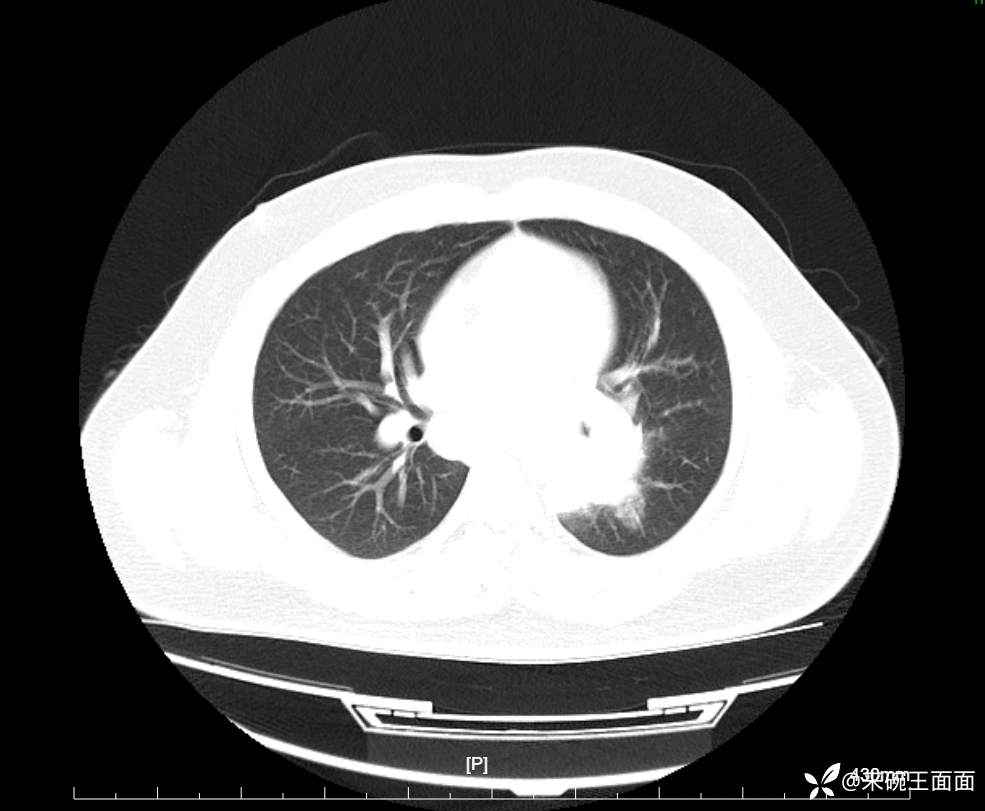

性别:男

年龄:27岁

主诉:胸闷胸痛数月余,休息后可自行缓解,无咯血症状。

个人史:数年吸烟史,具体不详。